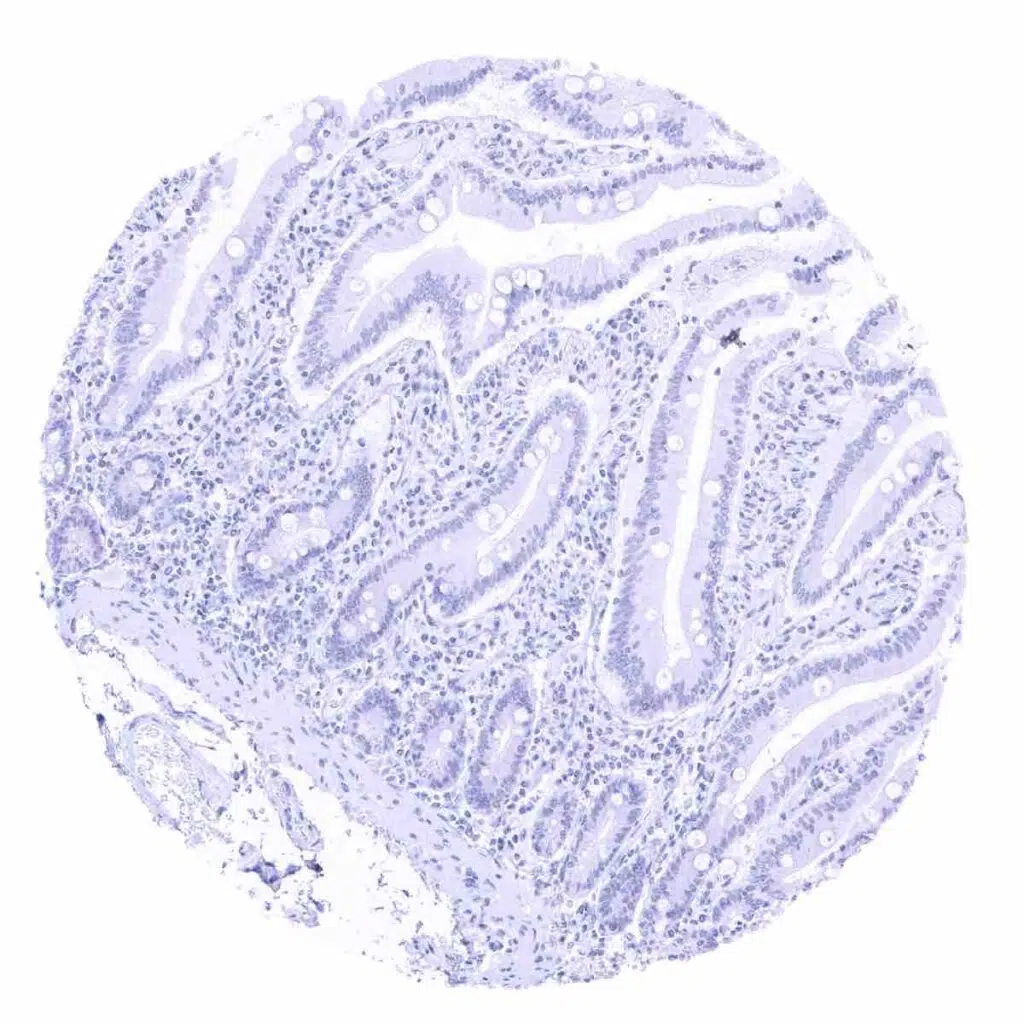

Duodenum, mucosa